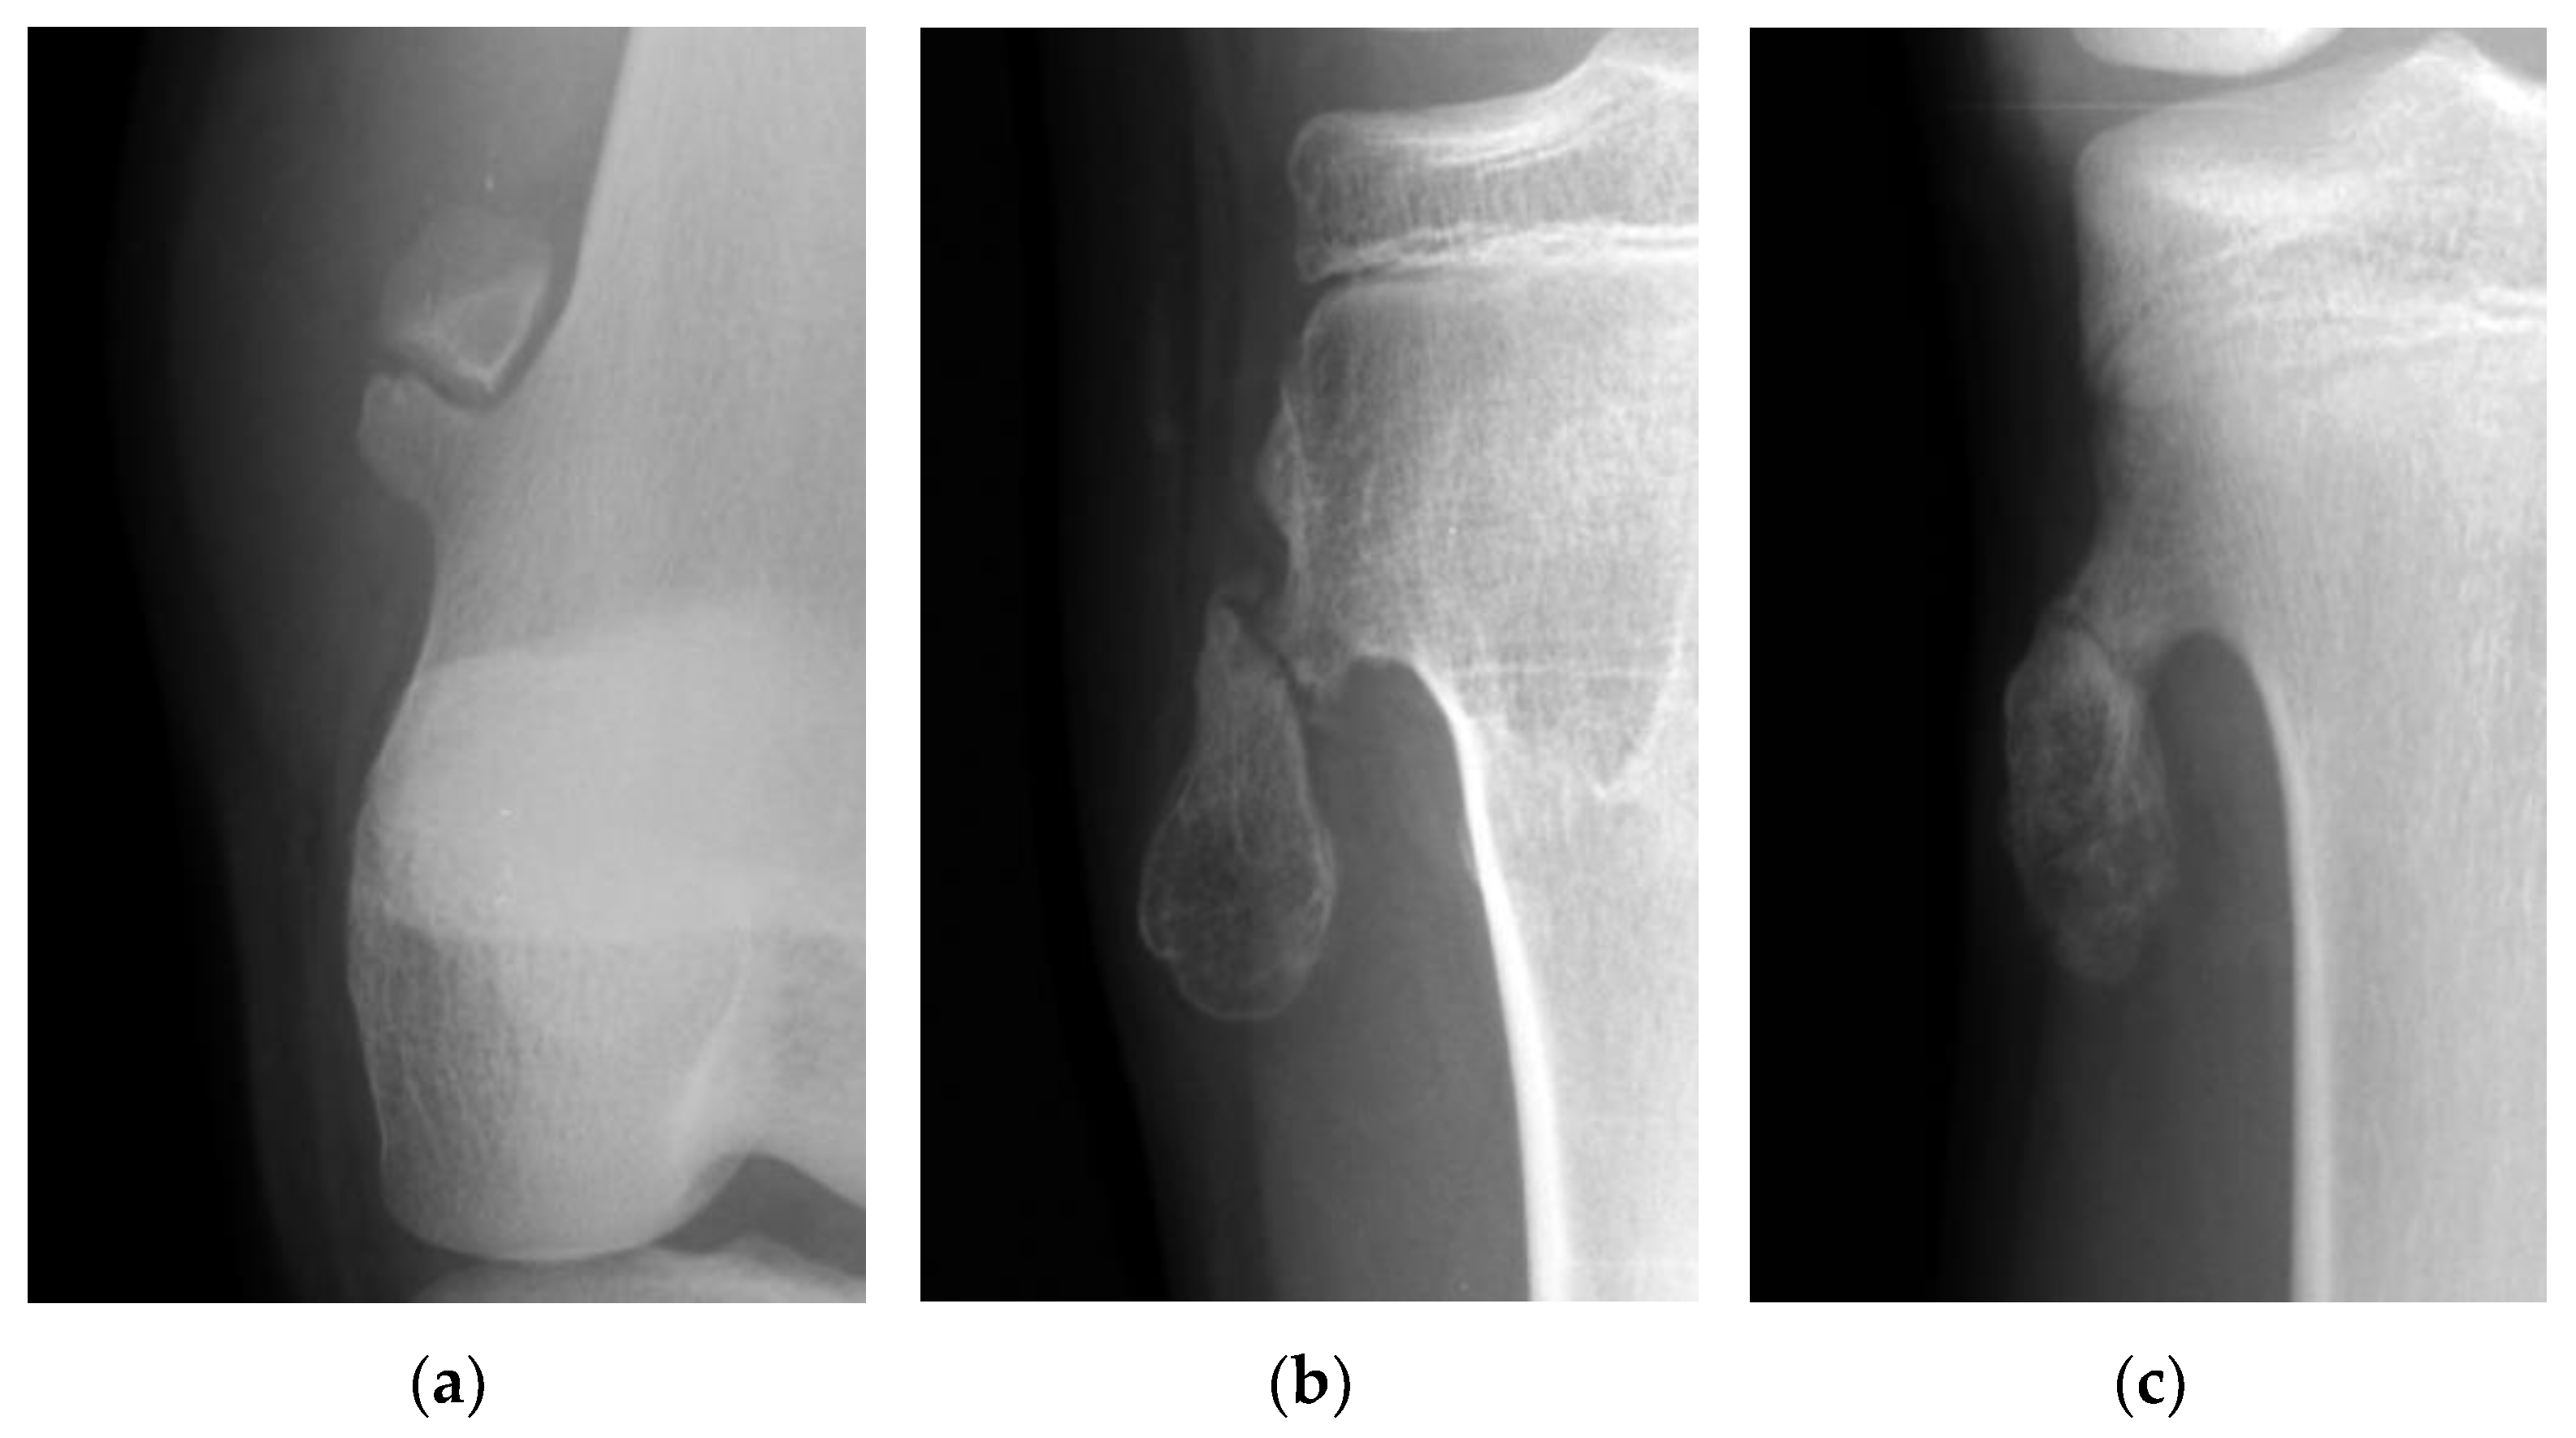

Figure 2. (a) The picture shows a gap widening of more than 1 mm between fragments of an osteochondroma in the femur. (b) The picture shows a more than 50% translation of a fractured osteochondroma in the tibia. (c) The picture shows a fractured osteochondroma in the tibia from the non-displacement group.

The fractures of the osteochondromas were divided into two types: displacement and non-displacement. In the present study, displacement was defined as a gap widening of more than 1 mm between fragments, or translation of more than 50% of the distal fragment in relation to the proximal fragment, either by anteroposterior, lateral, or oblique radiographic views of the knee joint (Figure 1). There were 12 patients in the displacement group and 11 patients in the non-displacement group (Figure 2).